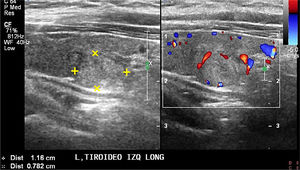

La ablación de nódulos sólidos con radiofrecuencia es una alternativa disponible para aquellos pacientes que no quieren o no pueden someterse a una intervención quirúrgica. Disponible hace más de 10 años en Corea y Europa, hace dos años ya se está realizando en nuestro país. Está indicada en nódulos con benignidad comprobada con al menos dos PAAF separadas en el tiempo por al menos 6 meses, que midan hasta 50mm de diámetro mayor (Figura 12a y 12b). Es un procedimiento ambulatorio, bajo anestesia local, bien tolerado, con resultados de disminución promedio de volumen de los nódulos de 79.7% a los 6 meses, con disminución significativa de los síntomas que motivaron la consulta inicial del paciente15.

Ablación de nódulo tiroideo benigno con radiofrecuencia.

A: Nódulo sólido, de 27.2mm de eje longitudinal (2.58 cc), levemente hiperecogénico, con dos PAAF negativas para células neoplásicas. Control pre ablación con radiofrecuencia (RF).

B: Control ecográfico a los 6 meses post ablación con RF del nódulo de la figura 17a El volumen del nódulo (0.51cc) disminuyó un 80%.